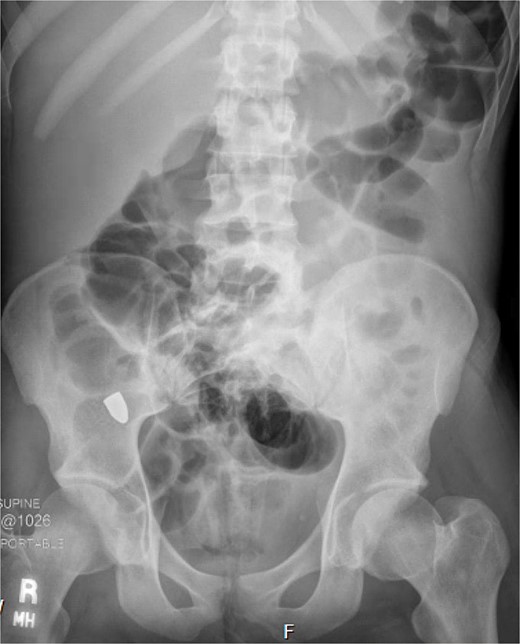

A 21-year-old male with a GSW to the left scapula presented to our Level 1 trauma center. He was stable but had flaccid paralysis and no rectal tone. A chest X-ray showed a bullet in the upper mediastinum (Fig. 1), prompting a computed tomography (CT) angiogram. The CT revealed a C6 cervical spine fracture, epidural hematoma, pneumomediastinum, and the bullet in the mediastinum at approximately the level of T3, but no hemorrhage (Fig. 2). Immediate upper endoscopy and bronchoscopy under general anesthesia were normal. He was extubated and monitored in the trauma ICU.

On hospital day (HD) 1, he developed ARDS and required intubation. He became hypotensive, raising concern for mediastinitis, but repeat imaging showed no new findings except that the bullet had migrated below the diaphragm (Fig. 3). Despite his septic appearance, his condition didn’t improve. He was diagnosed with severe AIDS (CD-4 count <100 cells/mm3) and multiple infections (hepatitis A, C, cytomegalovirus, toxoplasmosis, and multi-drug-resistant Pseudomonas pneumonia).

A repeat otolaryngology endoscopy exam on HD 2 revealed a 1.5 cm wound in the posterior pharyngeal wall, confirming the suspicion that the bullet entered the posterior of the mouth, was swallowed, and was now migrating down the GI tract. Serial X-rays tracked its transit (Fig. 4). Despite treatment, his condition remained critical. He underwent tracheostomy, gastrostomy, and diaphragmatic pacemaker placement. The patient was discharged to a long-term care facility on HD 22 but succumbed to complications from AIDS and pneumonia months later.